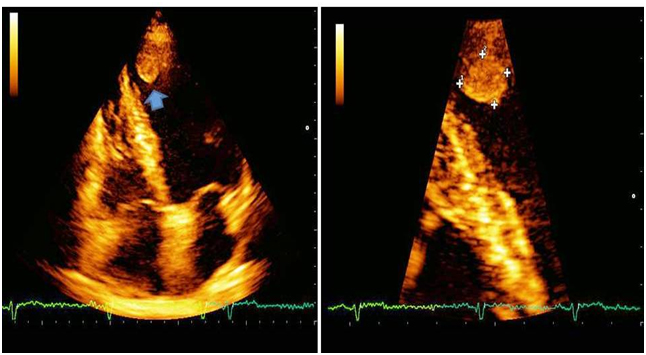

Detecting athletes with underlying heart disease is a great challenge for sports cardiology medicine. The goals of sports pre-participation screening are to prevent sudden death and other cardiovascular accidents in athletes. Herewith the author describes the history of an otherwise healthy 60-year-old amateur rider who came to our sports cardiology medicine center for sports pre-participation screening. His family history was unremarkable and physical examination was normal. He claimed he felt fit and that he was taking regular physical activity by cycling. His old ECG of 2014 was normal (Figure 1); the last ECG of 2015 (Figure 2) was abnormal for findings of recent anterior myocardial infarction. A subsequent echocardiogram through classical and magnified apical 4 chamber view showed left ventricular apical akinesis with small apical thrombus (Figure 3) which protrudes into the cavity and demonstrates mobility in real-time imaging (Videos 1 & 2). The athlete was admitted to cath lab for revascularization procedure and anticoagulation therapy was started.  The risk of cardioembolic stroke was very high. Trans-thoracic echocardiography (TTE) is usually the initial cardiac imaging modality, and reliably detects left ventricular wall motion abnormalities, and left ventricular thrombus. Nowadays, its use in sports cardiology medicine is mandatory to detect underlying and dangerous heart disease such as myocardial infarction complicated with LV thrombus in asymptomatic athletes [4].

Figure 3: Echocardiographic findings of left ventricular apical thrombus (see arrow and magnified imaging) by apical 4 chamber view.

Video 1 and 2:LV apical akinesis with small apical thrombus which protrudes into the cavity and demonstrates mobility by classical and magnified apical 4 chamber view.